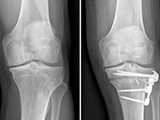

Osteotomia

Correção do eixo do joelho para redistribuição da carga articular.

Osteotomia do joelho